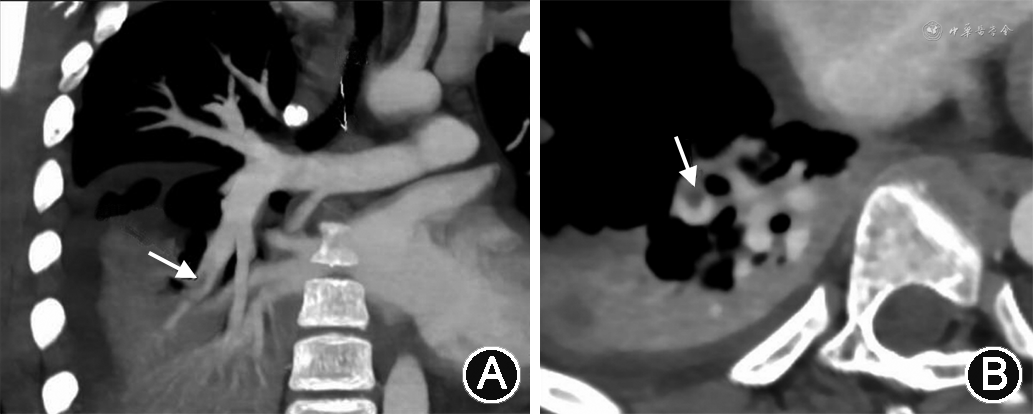

治疗经过:入院后急症行右髂骨骨髓炎开窗减压+肌间脓肿清理+封闭式负压引流(vacuum-assisted closure,VAC)术,术后体温仍有反复,予万古霉素、亚胺培南西司他丁抗感染。患儿术后26 h出现高热寒战,测体温41 ℃,心率159次/min,呼吸52次/min,血压159/139 mmHg,脉搏细数无力,四肢末梢凉,经皮血氧饱和度0.88~0.91,以“严重脓毒症”转至小儿重症医学科。急查血气分析示动脉血氧分压50 mmHg,诊断呼吸衰竭,予气管插管呼吸机辅助呼吸。床边胸X线片示符合支气管肺炎并右下肺实变表现。床旁超声心动图示三尖瓣探及轻度反流信号,估测肺动脉收缩压63 mmHg,因肺动脉高压原因不明,行心脏CT血管造影(CT angiography,CTA)示符合右下肺动脉栓塞表现(图1),同时完善双下肢动静脉血管超声未见异常。遂予依那肝素皮下注射抗凝,100 U/(kg·次),2次/d。患儿应用呼吸机辅助呼吸1 d后即撤机,未使用血管活性药物,但体温仍反复,第9天行左髋部探查+右髂骨骨髓炎清创换药+VAC负压引流术,第12天体温正常并转回小儿骨科。转科后改利伐沙班口服抗凝,15 mg/次,1次/d。入院1个月后复查CTA示原右下肺动脉部分分支管腔内原充盈缺损消失。住院36 d后好转出院,共应用万古霉素21 d,氟氯西林钠15 d。出院后继续口服利伐沙班1个月。随访至2021年1月,无不适。

儿童肺栓塞在临床上并不经常被诊断,但病死率高[1]。Gorenstein等[2]于2000年提出急性骨髓炎(acute osteomyelitis,AOM),深静脉血栓性静脉炎(deep venous thrombophlebitis,DVT)和脓毒性肺栓塞(septic pulmonary embolism,SPE)三联征。本例骨髓炎患儿入院前曾有胸痛,当时未考虑肺栓塞,未行超声、血管造影等特殊检查查找肺栓塞证据。术后出现严重低氧血症,血压高,超声心动图发现肺高压,经 CTA检查确诊肺栓塞。分析肺动脉高压与以下2个因素有关,一为栓塞后管腔狭窄,二为栓塞后继发缺氧性血管收缩,均可导致血管阻力增加。AOM病原学最常见为金黄色葡萄球菌[3],建议该病初始治疗应包括抗MRSA的糖肽类抗菌药物,疗程至少4~6周,后期可改为口服制剂[4]。肺栓塞患儿需仔细询问家族史,排除遗传性和获得性凝血功能障碍,如遗传性易栓症、抗磷脂综合征、高同型半胱氨酸血症等,这些疾病可能是DVT的诱因。全面的凝血功能检查包括同型半胱氨酸,蛋白C和S,抗凝血酶,凝血因子V,狼疮抗凝物,抗心磷脂抗体,脂蛋白A和β2糖蛋白抗体,必要时行凝血因子V相关leiden突变和凝血酶原G20210A变异基因检测[5]。肺栓塞的儿科治疗方案是从成人数据中推断出来的,第九版美国胸科医师学会指南建议抗凝治疗6周至3个月或直至继发性 PE 的诱发危险因素得到解决[6]。确诊肺栓塞后应立即应用普通肝素或低分子量肝素(low-molecular-weight heparin,LMWH)进行初始速效抗凝治疗,序贯使用 LMWH 或维生素 K 拮抗剂(vitamin K antagonist,VKA)。LMWH是儿童的首选药物,最常用的是依诺肝素,它的优势在于易于皮下给药、一般不需常规监测和半衰期更长[6, 7]。华法林是最常用的VKA,缺点包括需要根据饮食中的维生素 K 含量调整剂量、需频繁监测国际标准化比值,药物相互作用多[7]。本例患儿抗凝治疗共2个月,其中利伐沙班是一种新型口服抗凝药,与华法林相比,其优势在于起效快,吸收好,血药浓度稳定,不需定期监测凝血功能,但其用于儿童的安全性仍需进一步临床验证。溶栓、血栓切除术或取栓术适用于大面积肺栓塞和相关血流动力学不稳定的情况[1]。急性骨髓炎预后良好,早期、足量、足疗程使用抗菌药物,结合抗凝、手术清创和必要时机械通气大多可获得成功。儿科医生在接诊AOM患儿时,对合并呼吸系统症状者,尤其在术后突发状况恶化,包括呼吸困难、血压改变等需考虑AOM、SPE和DVT三联征,及时进行肺部相关影像学检查以评估肺部受累情况,以免延误诊断和治疗。CTA检查操作便捷,能够显示肺动脉血管栓塞的位置和程度,可作为首选,并可结合超声心动图和多普勒超声辅助诊断。